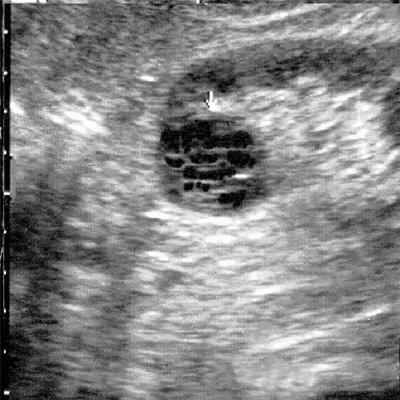

(Справа) На УЗИ в сагиттальной плоскости выявлено покрытое капсулой многокамерное кистозное образование верхнего полюса почки, выступающее непосредственно в почечный синус.

УЗИ в В-режиме. Мультилокулярная киста почки.

В диагностике мультилокулярных кист ценные сведения можно получить при помощи ультразвукового исследования (УЗИ). По данным разных авторов, достоверность УЗИ в диагностике данной патологии составляет от 94 до 97,3% [1, 8, 9, 11-13]. Эхографически мультилокулярная киста визуализируется в виде многокамерного жидкостного образования округлой формы, расположенного в одном из полюсов почки, с множеством перегородок, как правило, с отложением извести, с четкими ровными контурами и дорсальным усилением эхо-сигнала (рис. 2) [1-3, 6, 8, 9, 12, 14]. Цветное допплеровское картирование (ЦДК) увеличивает чувствительность УЗИ, так как улучшает визуализацию областей с атипичной сосудистой архитектоникой и снижением васкуляризации. При допплерографии отмечаются неспецифические изменения почечного кровотока в виде повышения пульсационного индекса и индекса резистентности, особенно выраженных в сосудах, огибающих образование. Если при УЗИ обнаруживаются утолщение перегородок кист или солидные структуры, в которых при ЦДК регистрируются сосуды, это может быть признаком малигнизации [11, 13, 15-19].

Эхонегативное многокамерное образование неправильной формы, с неровными стенками. Большое количество тонких перегородок в полости образования.

Округлое кистозное образование с множеством перегородок в полости образования и единичным кальцинатом.